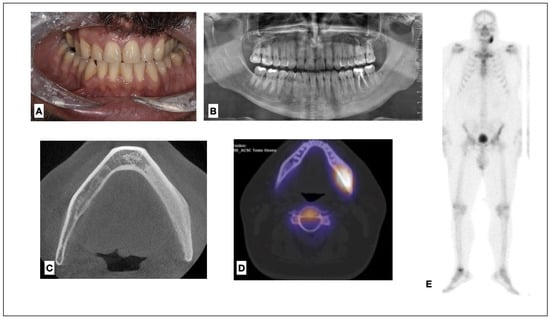

2.2. Patient 2